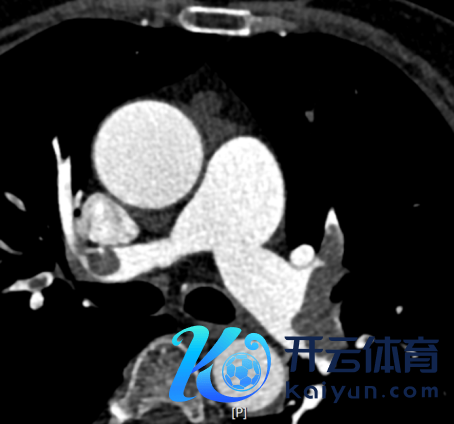

强化CT扫描刚完结,CT见“双肺动脉、双侧各叶段动脉内见多发条片状低密度充盈缺损,冠状动脉前降支局限性非钙化斑块,管腔轻微褊狭”(图3-5)。

图3.CTPA成果